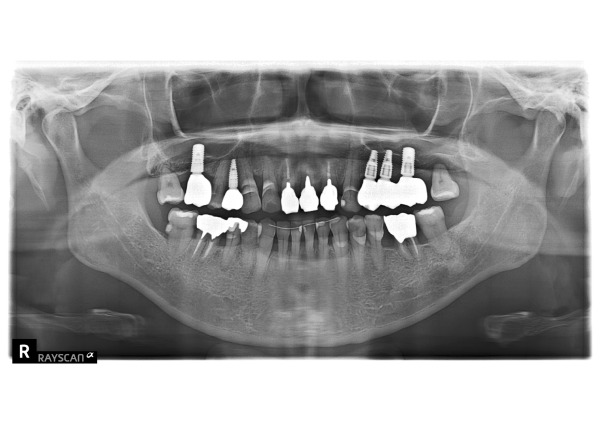

エックス線で撮影したところ、患者様は歯周病も進行しており、全体的に骨が吸収して歯根の半分まで減ってしまっていました。

特に、左右7番の骨が著しく減っており、左上の奥歯は歯根まで骨が吸収し、残すことが不可能な状態でした。

前歯3本は神経がなく、痛みはないものの、歯ぐきが下がったことで茶色く変色した歯根が見えてしまっている状態でした。見た目を気にされていた患者様に治療の選択肢をご提案したところ、「被せ物の色を細かく再現できる」という理由からジルコニアセラミックの被せ物を選択されました。